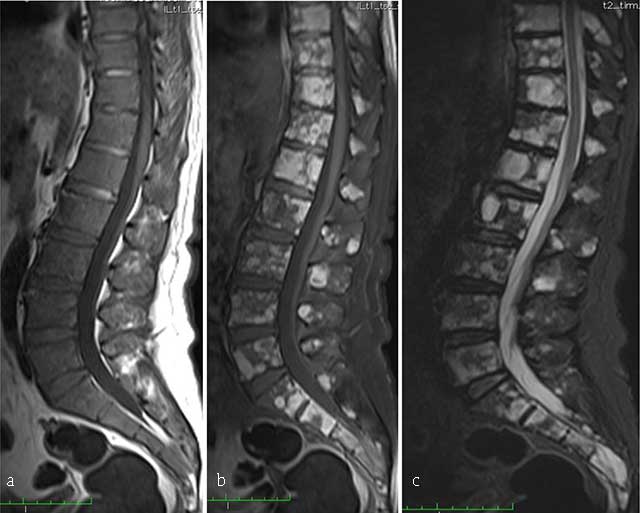

Figure 11

Multiple myeloma. MR: (a) Sagittal T1-WI, (b) sagittal fat-suppressed T1-WI after gadolinium contrast administration and (c) sagittal fat-suppressed T2-WI of the thoracolumbar spine display a diffuse bone marrow infiltration of vertebrae with low signal intensity on T1-WI and intermediate to high signal intensity on T2-WI. There is multifocal enhancement.